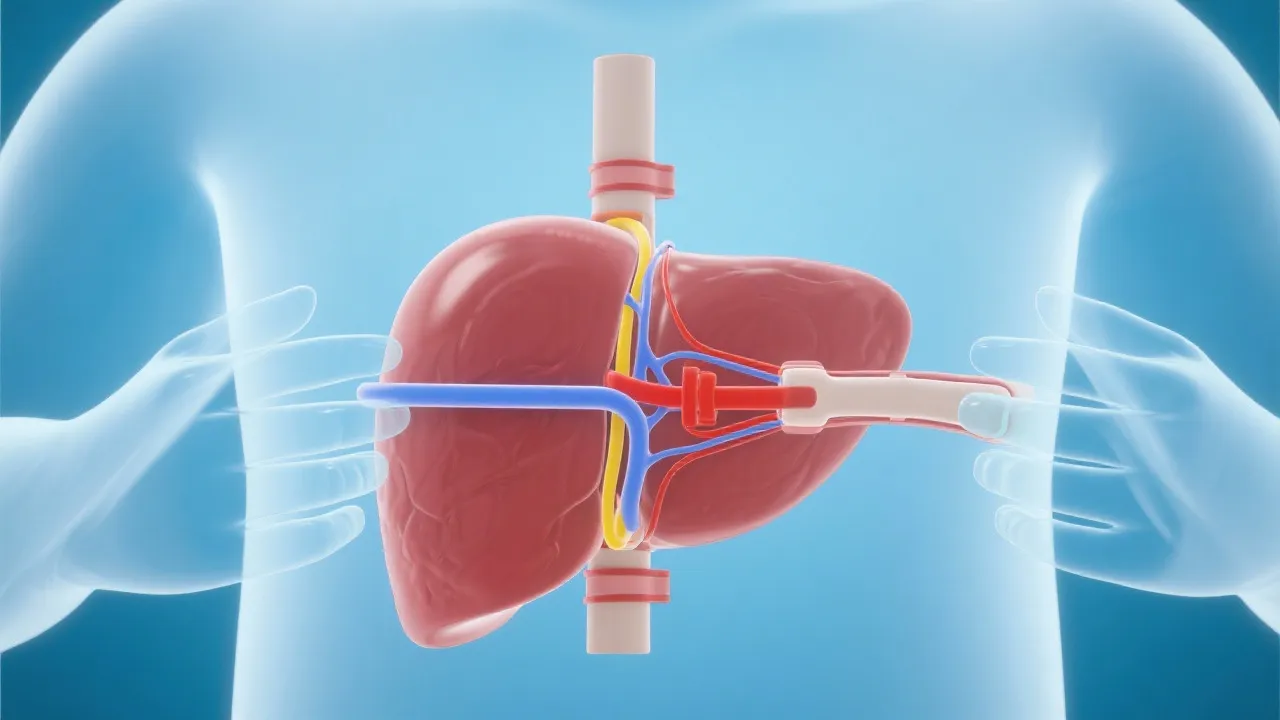

The liver transplant procedure involves the replacement of a diseased liver with a healthy liver from a deceased or living donor. The surgical technique requires meticulous planning and execution, involving a multidisciplinary team of specialists, including surgeons, anesthesiologists, and transplant coordinators. Advancements in surgical techniques and post-operative care have significantly improved patient outcomes, enhancing survival rates and quality of life. Transplantation itself involves several critical phases, starting from pre-operative assessment, surgical intervention, and extended post-operative care, all of which are key to ensuring a successful outcome.

One of the main challenges in liver transplantation for NASH patients is the scarcity of donor organs. In many regions, the demand for liver transplants significantly exceeds the availability of suitable donors, leading to extensive wait times for patients in need. This has spurred the exploration of innovative approaches, such as utilizing marginal livers—organs that may be deemed less than ideal due to age or minor dysfunction—or studying bioengineered organs crafted from a patient’s own cells. Additionally, addressing underlying metabolic conditions and lifestyle modifications remain essential components of pre- and post-transplant care.

Innovative strategies are continually being explored to optimize organ usage. For example, expanded criteria donor (ECD) livers, which include livers from older donors or those with certain health issues, are being evaluated in clinical data to ensure they can be viable options. Living donor transplantation also offers an alternative route, allowing a healthy individual to donate a portion of their liver to a recipient. This not only increases the available organs but can also reduce waiting time, thus saving lives.